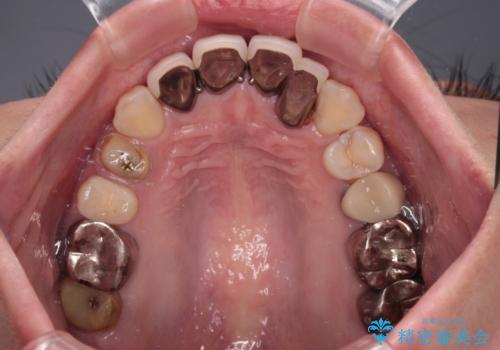

むし歯で神経を取り除いたことをきっかけに、前歯をセラミックにしたそうですが、金属の縁が見えてきたり、内側に引っ込んでいた歯を強引に前に出しことで汚れが溜まったりと、不具合を感じているとのことでした。

また、奥歯にも痛みがあったり治療途中で放置されていたりと、全顎的な治療が必要な状況でした。

結婚式が近いことから、前歯は舌側に転位している歯は抜歯してブリッジにすることで外見と清掃性を改善し、速やかにオールセラミッククラウンにて補綴治療を行うこととしました。

その後、奥歯は痛みのある部分から少しずつ、根管治療やインプラント治療などを行うこととしました。